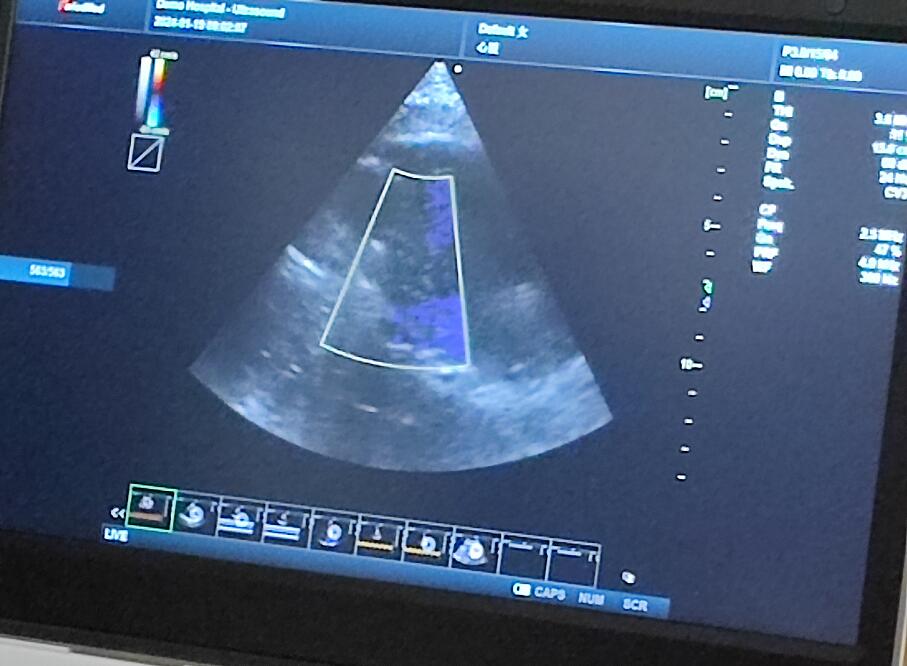

當(dāng)天的超聲培訓(xùn)現(xiàn)場(chǎng)氣氛熱烈非凡,來(lái)自普邁思醫(yī)療事業(yè)部的同仁們紛紛積極參與,滿懷期待地聚集在講臺(tái)周圍,他們的眼神充滿了對(duì)新知識(shí)的渴望和對(duì)技術(shù)提升的執(zhí)著追求。老師身邊里三層外三層圍滿了學(xué)員,大家或是聚精會(huì)神聆聽講解,或是踴躍提問(wèn),交流互動(dòng),濃厚的學(xué)習(xí)氛圍讓整個(gè)場(chǎng)地顯得熱鬧非凡,盡管空間狹小,但阻擋不住的是每一位參與者內(nèi)心深處對(duì)于專業(yè)技能提升的決心與毅力。

授課的專家老師被這股澎湃的學(xué)習(xí)熱情深深打動(dòng),她的臉上洋溢著欣慰和鼓舞的笑容。面對(duì)這樣一群如饑似渴的學(xué)子,老師更是傾盡全力,毫無(wú)保留地將自己豐富的臨床經(jīng)驗(yàn)和深厚的專業(yè)理論知識(shí)悉數(shù)傳授,詳細(xì)解答每一個(gè)問(wèn)題,用心指導(dǎo)每一次操作演練。她表示,普邁思醫(yī)療事業(yè)部團(tuán)隊(duì)展現(xiàn)出的這種敬業(yè)精神和積極向上的風(fēng)貌讓她深受感染,還給予了他們高度評(píng)價(jià)和嘉許。